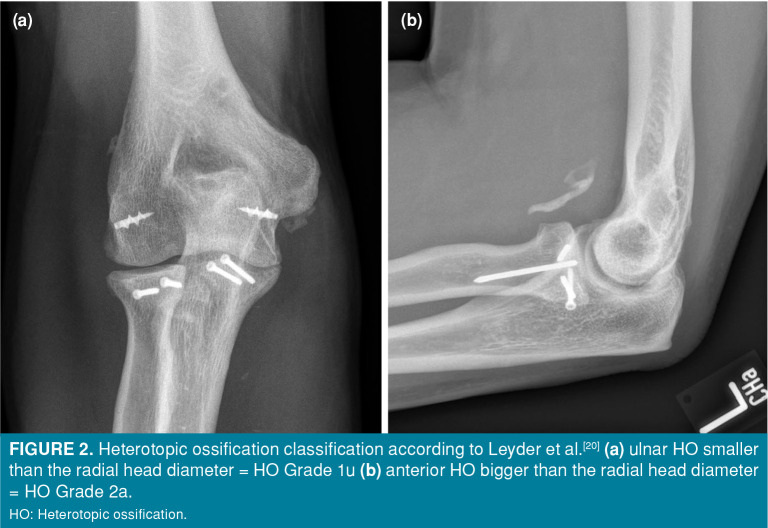

Patients and methods: In this retrospective study, 73 patients (40 males, 33 females; mean age: 51.4±15 years; range, 20 to 82 years) with Mason-Johnston type 3 and 4 radial head fractures were surgically treated with osteosynthesis or radial head arthroplasty (RHA) between September 2014 and February 2021. Fifty-one were examined in person, while 22 participated via questionnaire. The clinical outcome was assessed by the range of motion, the Disabilities of the Arm, Shoulder, and Hand questionnaire (DASH), and the 36-item Short-Form Health Survey (SF-36). Operative and postoperative details and the intake of HO prophylaxis were reviewed. Heterotopic ossification severity and location was evaluated on radiographs.